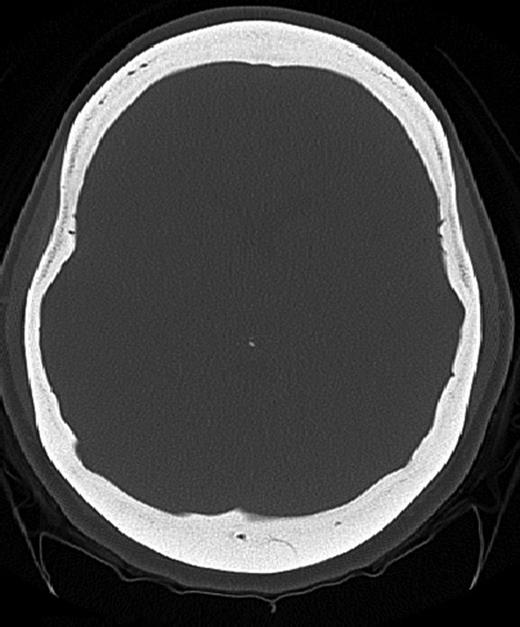

Axial CT image (bone window) showing diffuse calvarial thickening and loss of the medullary space.